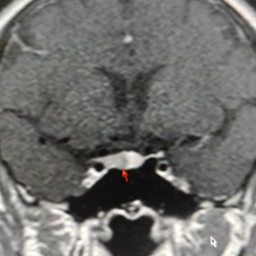

箭头位置为李女士脑部垂体瘤。

为查清病因,李女士住院治疗,王敏主任医师带领医疗团队开始了缜密的诊断过程,最终诊断指向ACTH依赖性库欣综合征——垂体ACTH瘤,该病的患者因ACTH过度分泌引发皮质醇增多症,典型症状包括向心性肥胖、满月脸、皮肤紫纹及代谢异常,可合并糖尿病、性腺功能抑制等并发症。由于肿瘤体积微小(通常直径毫米),CT及MRI(核磁共振)检出率较低,诊断主要依赖内分泌学检查。